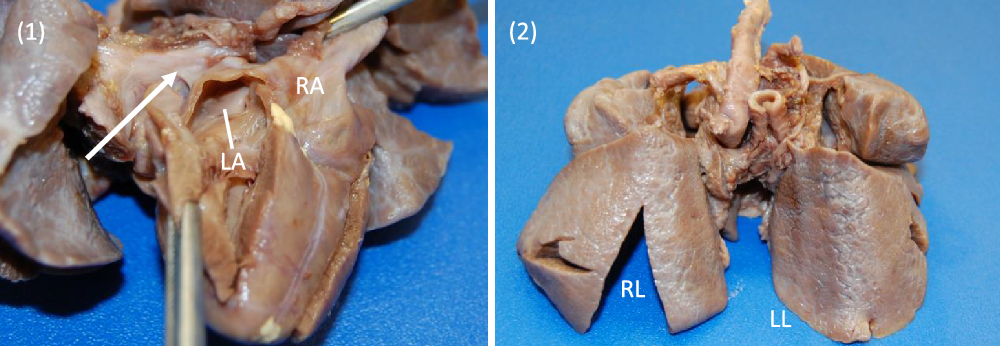

On arrival, the patient remained on an alprostadil infusion at 0.1 mcg/kg/minute, with oxygen saturations persistently in the 50’s despite ongoing respiratory support with nasal continuous positive airway pressure with FiO2 100%. The patient was immediately intubated but remained significantly desaturated. Repeat echocardiogram was obtained (Fig 1), which revealed the absence of pulmonary veins entering the atrium and absence of dilated pulmonary veins or large vertical vein. There was all right to left shunting across an unrestrictive atrial communication, and there was a large patent ductus arteriosus with predominantly right to left flow. A trivial pulmonary vein confluence was seen posterior to the left atrium. The right ventricle was dilated and the left ventricle was apex forming but appeared underfilled. Given that discrete pulmonary veins or venous drainage could not be delineated by echocardiography, cardiac CT scan was emergently obtained. Cardiac CT revealed a trivial pulmonary venous confluence with small left and right veins posterior to the left atrium; however, no discrete connection to the heart was identified (Fig 2). Due to the near atretic nature of this patient’s pulmonary veins and common pulmonary vein and lack of identified collaterals, extensive multidisciplinary discussions were held between Cardiology, Cardiac Intensive Care, Radiology, and Cardiothoracic Surgery teams. Ultimately, it was determined that there was no viable operative repair, and the decision was made between the family and the medical team to proceed with withdrawal of care. The patient was transferred back to the cardiothoracic ICU, compassionately extubated, and died shortly thereafter. An autopsy was performed which confirmed the absence of any pulmonary venous connection to the left atrium. There was a trivial pulmonary venous confluence superior to the left atrium as noted on the echocardiogram and CT, with a trivial vein that appeared to drain from the confluence to the innominate vein. No dilated pulmonary veins were demonstrated by autopsy. On gross examination, the lungs had a diffusely nodular appearance and histological examination revealed findings consistent with cystic lymphangiectasia.

Images 1, 2. Gross specimen images. (1) Posterior view. A trivial pulmonary venous confluence is seen superior to the left atrium (arrow). The left atrium has been reflected open and there is no identifiablepulmonary venous drainage entering the left atrium. The right atrium is notably dilated. (2) Anterior view. The lungs have a diffusely nodular appearance consistent with the post-mortem microscopic findings of cystic lymphangiectasia.